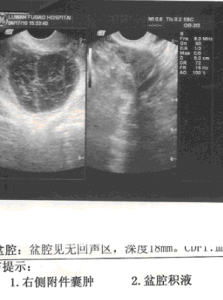

3.宮頸粘液或子宮內膜活檢,有正常的組織分泌象,即顯示黃體期改變,血孕酮水平≥3ng/ml即可診斷。B超連續追蹤卵泡,有成熟卵泡但無排卵;